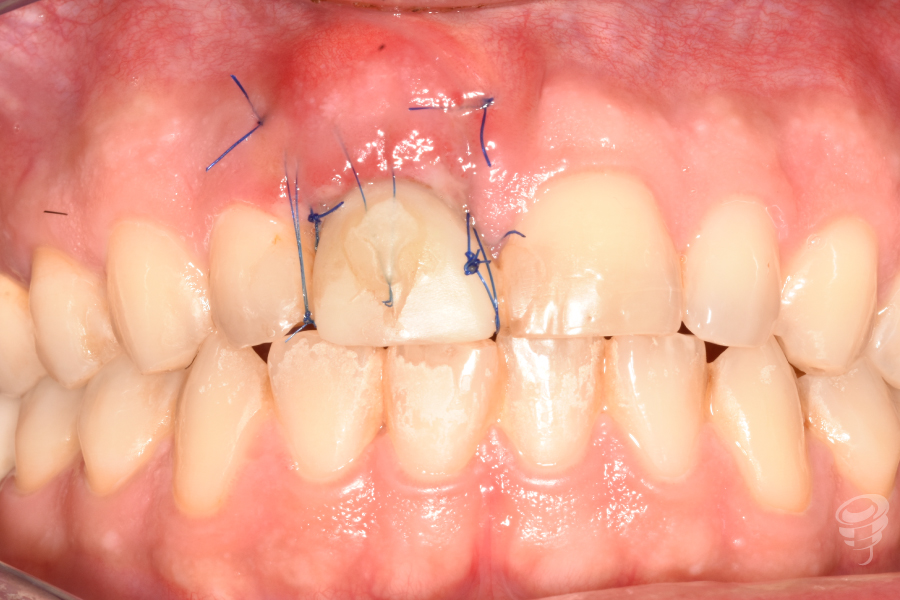

- Provisionalización: Pilar titanio personalizado + corona provisional de resina acrílica (sin contacto oclusal), con la colocación de puntos suspensores para estabilizar la encía y márgenes gingivales.

- Corona provisional implanto-soportada realizada con una corona de resina en «cáscara de huevo», para arrastrar al pilar inmediato, se realiza el contorneo y perfiles de emergencia a mano alzada.